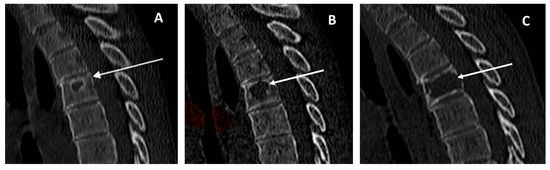

Imaging Analysis for Metastatic Risk Assessment in Adamantinoma: The Aid of Radiology in the Absence of a Histological Grading—An MRI-Based Risk Model Proposal

Background: Adamantinoma is a very rare primary malignant bone tumor. A histopathological grading is still lacking, and as a result, metastatic risk stratification at diagnosis is challenging. Due to this, imaging could play a role in prognosis prediction and treatment strategy assessment. We aimed to evaluate baseline imaging features and their correlation with the development of metastatic disease. Methods: We retrospectively collected clinical (metastatic disease) and radiological data at baseline (Conventional Radiography, CT, MRI) of all consecutive patients with a histopathological diagnosis of adamantinoma at our sarcoma center between 2006 and 2022. Tumor location, dimensions, main radiological pattern (lytic, sclerotic, mixed), Lodwick–Madewell grading, periosteal reaction, multifocality, soft-tissue extraskeletal component, peritumoral edema, peritumoral enhancement, and vascular invasion were analyzed. Associations between the above-mentioned radiological features and metastatic disease at diagnosis or during follow-up were assessed. Results: Twenty-two patients were included (15 [68.2%] women, median age 27 years old, range 7–58 years old). Six out of twenty-two patients (27.3%) developed distant metastases (only two of them were dedifferentiated adamantinoma): two patients (9%) presented with metastatic disease at diagnosis, while four patients developed metastases during follow-up (18.2%). The following radiological features represent a significant risk for metastatic disease (p = 0.01): (i) presence of an extra-skeletal component (Odds Ratio [OR] = 75.40; 95% CI = 3.15–1802.71), (ii) vascular invasion (OR = 121.00; 95% CI = 4.28–3424.73), (iii) diffuse peritumoral edema (OR = 75.40; 95% CI = 3.15–1802.71), (iv) peritumoral enhancement (OR = 84.33; 95% CI = 2.93–2423.26). All other features analyzed were not significantly associated with the onset of distant metastases. Based on these above-mentioned MRI features, we built two risk models for metastatic disease (excluding peritumoral enhancement, which was not available in five patients, to be applicable on unenhanced MRIs): Model (A) = simultaneous presence of two of those three features (2/3) with a sensitivity of 100% (54.07–100%) and a specificity of 93.75% (69.67–99.84%). Model (B) = simultaneous presence of all three features (3/3) with a sensitivity of 83.33% (35.88–99.58%) and a specificity of 100% (74.1–100%). Conclusions: An accurate evaluation of baseline imaging studies (particularly MRI) in patients affected by adamantinoma may significantly aid in prognosis prediction and the selection of high-metastatic-risk patients. For these patients, strict follow-up controls and more aggressive treatments should be suggested after multidisciplinary discussions in sarcoma centers. Full article

Show Figures

Figure 1